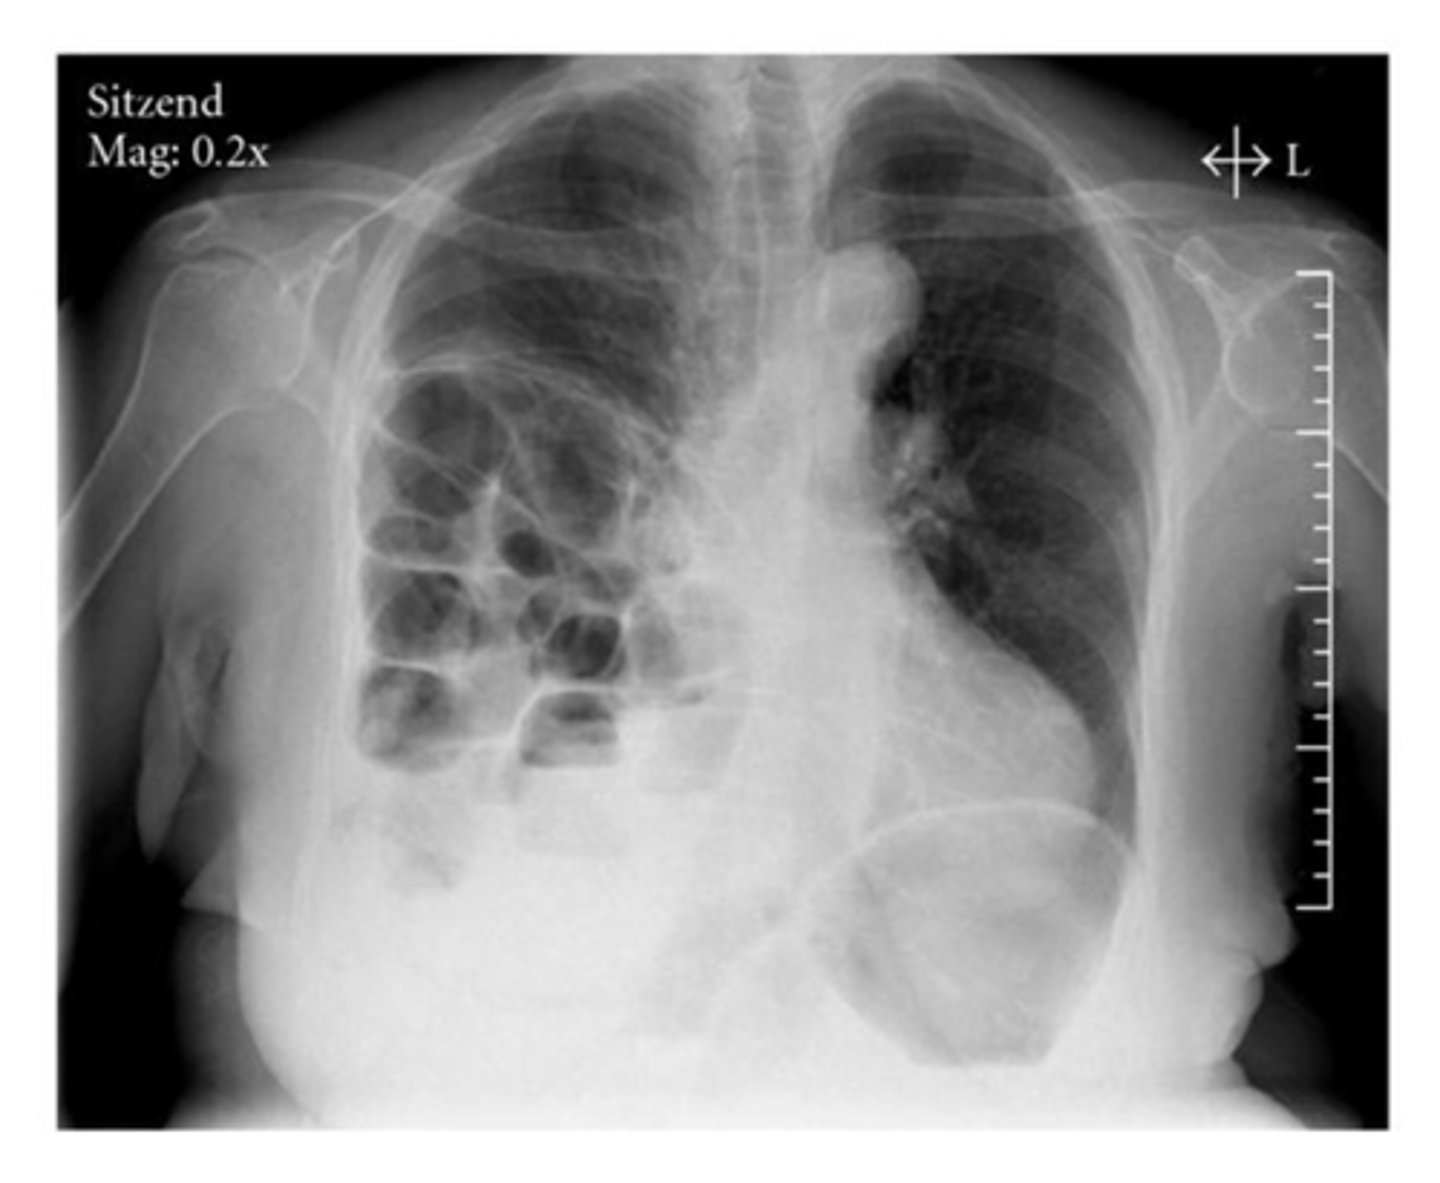

Diaphragmatic rupture

knowt flashcard image

Diaphragmatic hernia